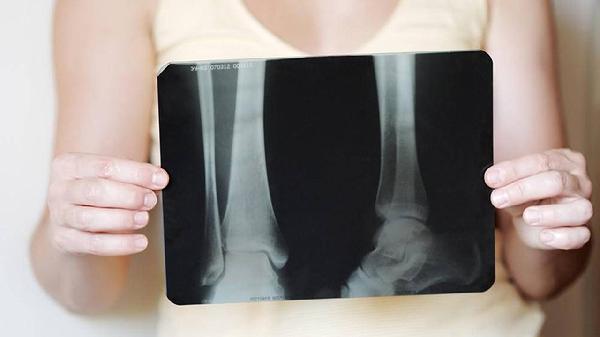

四妙丸由苍术、黄柏、牛膝、薏苡仁组成,具有清热利湿、通络止痛的功效。中医理论认为筋骨疼痛多与湿热下注、经络阻滞有关,该药通过祛除湿热、舒筋活络发挥作用。临床常用于湿热型关节炎、腰椎间盘突出等引起的筋骨酸痛,对伴有下肢沉重、关节红肿热痛的症状可能有一定缓解作用。

但筋骨疼痛病因复杂,若由骨折、肿瘤、风湿性关节炎等非湿热证型引起,或患者存在脾胃虚寒、阴虚火旺等情况,则不宜使用。孕妇及过敏体质者也需禁用。部分患者服药后可能出现胃肠不适,需及时停药就医。